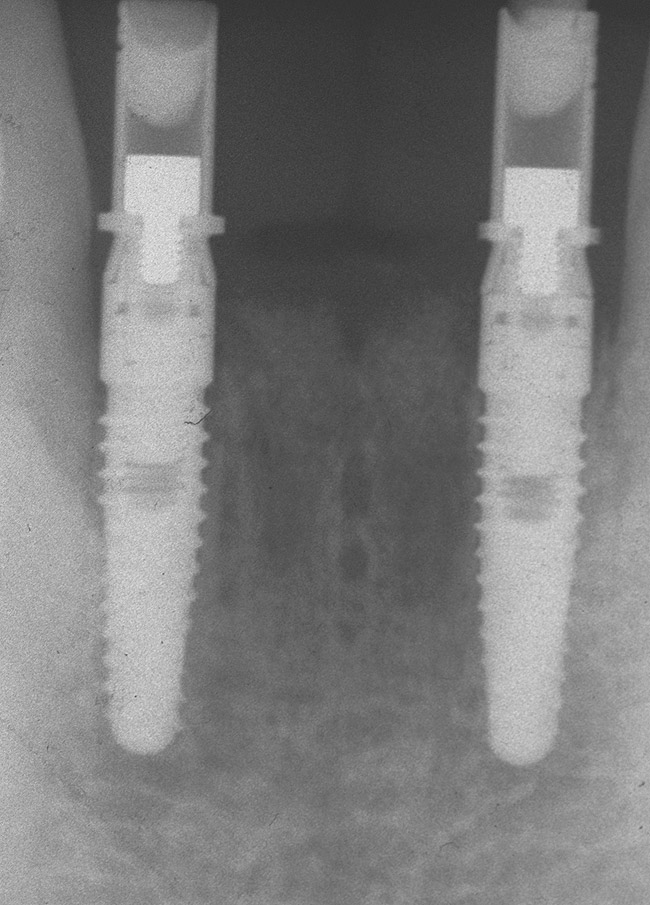

Preoperatively, 1 g of amoxicillin was administered. Using local anesthesia (lidocaine 1:100,000 epinephrine), extractions of teeth No. 23 to No. 26 were performed without raising a flap and with gentle luxation to preserve the remaining facial osseous plate. The sockets were curetted prior to implant placement. A vacuum-formed surgical guide, fabricated based on a diagnostic wax-up of the desired tooth positions for the subsequent fixed prosthesis, was used during implant placement. Osteotomies were performed at sites No. 23 and No. 26 and positioned toward the lingual aspects of the sockets (Figure 3A and Figure 3B). Two tapered implants (OsseoTite™ 313, BIOMET 3i™, Palm Beach Gardens, FL) measuring 3.25 mm x 13 mm were placed. Conical prosthetic abutments (3-mm height) were used to facilitate joining the two implants in a screw-retained fixed partial denture (Figure 4). A laboratory-processed acrylic-resin provisional restoration was altered to allow connection to the temporary cylinders. The provisional was placed into the vacuum-formed surgical guide that was now used to maintain the provisional in the correct 3-dimensional position (Figure 5) while being attached to the temporary cylinders with acrylic resin intraorally. Once a sufficient amount of acrylic resin was placed to secure the cylinders to the provisional, it was removed from the mouth and its contours were completed at the laboratory bench (Figure 6A). The two central incisor sockets were grafted with small-particle allograft material (Puros® Allograft, Zimmer Dental, Carlsbad, CA) to maintain gingival architecture beneath two ovate pontics (Figure 6B). The provisional restoration was inserted and the screws tightened to 20 Nt-cm of torque.

The patient was given postoperative instructions and advised to maintain a soft diet for 6 to 8 weeks to protect the implants. The patient was followed weekly for the first 3 weeks and monthly thereafter. After 4 months of healing, the provisional restoration was removed and the soft tissues were examined. Mature, keratinized gingival tissues were present facially, lingually, and interproximally. Nonkeratinized tissue could be seen at the tissue surfaces of the ovate pontics and in the intrasulcular regions of the implant abutment units. No clinical probing depths beyond 1 mm were found adjacent to the abutments. The healed tissue represented an acceptable clinical result especially in light of the gap that had been present at the time of implant placement (Figure 7A and Figure 7B). Final impressions were made, and the permanent ceramo-metal screw-retained prosthesis was placed within 8 weeks (Figure 8).

This patient has been followed for 4 years with no complications and no discernable clinical changes in soft- or hard-tissue levels.

Figure 4  Tapered implants with conical transgingival abutments and temporary cylinders in place.

Figure 4

Figure 9  The 4-year postoperative radiograph.

Figure 9